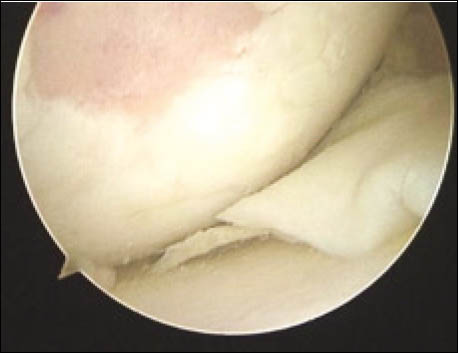

Figura 8: Abordaje anterior reducido 2° mes postopera- torio.

Figura 9: Extensión activa 2° mes postop

Figura 10: Flexión completa, 2° mes postop.